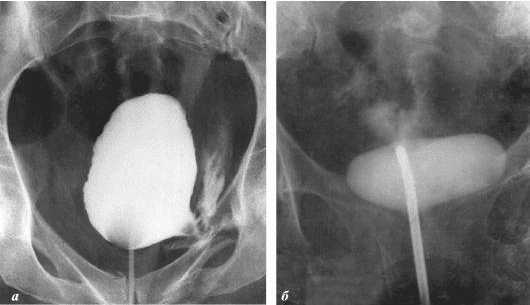

Želim da vam pokažem neke fotografije tako da sami možete da vidite šta se dešava urogenitalnom sistemu i drugim organima muškarca koji nema seksualne odnose.

Evo kako izgleda upala prostate uzrokovana stagnacijom sperme (kada se testisi ne prazne). Trajna upala dovodi do adenoma prostate, a kasnije do raka prostate (prema statistikama, 38% muškaraca umire zbog ovoga). Zbog odsustva seksa, ovo se dešava uvek i to je razlog zašto se adenom prostate naziva "bolešću starih".